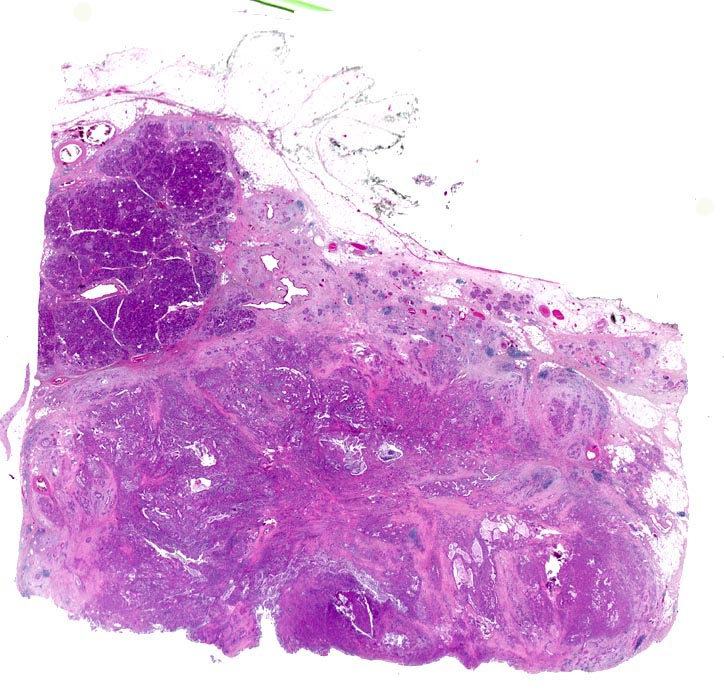

• Unregelmässige Anordnung der Drüsen (keine Läppchenarchitektur erkennbar).

• Kribriforme Drüsenformationen.

• Inkomplette Drüsen mit unvollständigen Lumina und Infiltration des Stromas durch Tumoreinzelzellen.

• Nekrotische Tumorzellen in den Drüsenlumina.

• Ausgeprägte Polymorphie und Hyperchromasie der Tumorzellkerne.

• Desmoplastisches Stroma.

• Rechts oben Reste von nicht neoplastischem Pankreasparenchym mit fokaler chronisch obstruktiver Pankreatitis als Folge von tumorbedingten Gangobstruktionen: Vollständige Atrophie des exokrinen Pankreas bei erhaltenen Inseln. Ersatz des atrophen Parenchyms durch Fibrose. Chronisches Entzündungsinfiltrat.